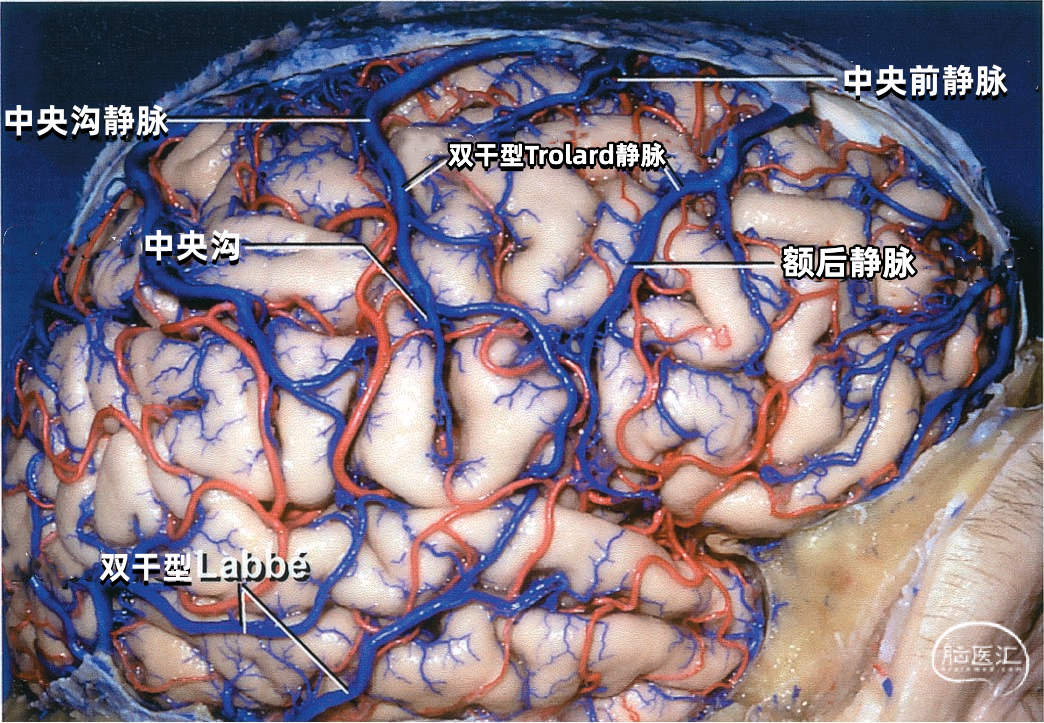

大脑外侧面最大的静脉是Trolard、Labbé、外侧裂浅静脉。 Trolard静脉是最粗大的吻合静脉,连接外侧裂静脉和上矢状窦。Labbé静脉则是连接外侧裂浅静脉和横窦的最粗大吻合静脉。外侧裂浅静脉沿外侧裂表面走行,而且主要沿蝶骨嵴汇入硬膜窦(蝶顶窦或海绵窦)。 虽然Trolard、Labbé静脉和外侧裂浅静脉大小可能相同,但更常见的是其中一支或两支血管比较粗大,而剩下的则细小甚至缺如。通常左右两侧血管的大小并不对称。

▼1.Trolard静脉

Trolard静脉又称上吻合静脉,是跨越额叶和顶叶,连接外侧裂与上矢状窦的最大吻合静脉。 在我们研究的20例半球标本中,发现15例Trolard静脉的位置相当于中央前静脉、中央沟静脉和中央后静脉,最常见的位置是中央后静脉水平。最靠前的Trolard静脉位于额前静脉水平,连接上矢状窦的前部和外侧裂浅静脉的前部。最靠后的Trolard静脉位于顶前静脉水平。 Trolard静脉通常以单干向前走行,汇入上矢状窦,与血流相反方向。通常Troland静脉在将要汇入上矢状窦前接受其他一些静脉的回流,它的下端通常以单一通道与外侧裂静脉相沟通,但也可在额叶和顶叶凸面的下部分成许多分支加入外侧裂浅静脉。有时会有两条同样大小的Trolard静脉连接外侧裂血管和上矢状窦之间。

下图示(左侧半球)外侧裂浅静脉与Labbé静脉之间有较大的吻合支。另外,有两支或双干型的Trolard静脉属支连接上矢状窦和外侧裂静脉,后方一支Trolard静脉在外侧裂浅静脉与Labbé静脉的结合处附近加入外侧裂浅静脉。

下图示(右侧半球)双干型的Trolard静脉连接于上矢状窦和外侧裂之间,一支越过额叶,另一支越过顶叶。外侧裂浅静脉与Labbé静脉之间也有一个粗大的吻合支。

下图示(右侧半球)没有明显的外侧裂浅静脉。有双干型Labbé静脉从外侧裂到横窦。中央沟静脉和额后静脉的大小几乎相同,组成双干型Trolard静脉,连接外侧裂和上矢状窦。中央沟静脉下部走行于中央沟内。

下图示双干型Trolard静脉和双干型Labbé静脉引流外侧裂附近的大部分静脉。